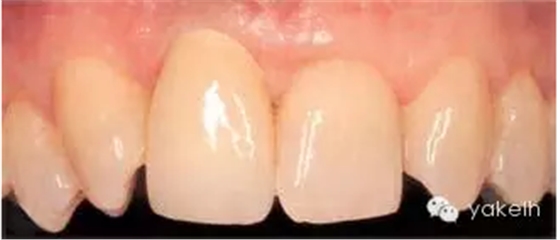

患者先天缺失側(cè)切牙,同時(shí)由于外傷UR1缺失。UR1種植修復(fù)。該種植冠大約有2mm 的牙齦退縮,與UL1相比,該修復(fù)冠較長(圖.8A)。這是由于種植體植入位置過深而導(dǎo)致的(圖.8B)。

圖.8 種植體植入過深,引起牙齦退縮以及修復(fù)冠過長。